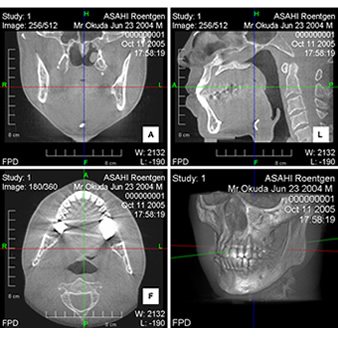

症例

- 症状:上顎小臼歯部の自発痛、咬合痛

デンタルX線像では良好に処置された無髄歯ですが、DentalCTでは第一小臼歯、第二小臼歯に未処置の根管を認め、再治療後症状は消退しました。

第1、第2小臼歯の未処置根管

第1、第2小臼歯の再根管治療後